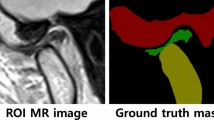

The notable sensitivity of the PVA-EBPD hydrogel sensor in monitoring limb joint and TMJ activity in pigs suggests its potential utility in detecting human TMJ activity and serving as a diagnostic tool for TMD. To evaluate the feasibility of using the PVA-EBPD hydrogel sensor for monitoring TMJ activity and assisting in DDwR diagnosis in humans, 120 volunteers (median age: 24 years; range: 19–54 years) were enrolled in this study based on the inclusion and exclusion criteria (Supplementary Table 7). No participants withdrew from the study. The baseline characteristics of participants are summarized in Supplementary Table 8. All volunteers were previously diagnosed with either normal TMJ or DDwR by TMJ specialists at West China Hospital of Stomatology, Sichuan University. TMJ-related histories and clinical examination findings were documented in accordance with Supplementary Table 9. According to the clinical diagnosis, the volunteers were divided into a normal TMJ group (n = 58) and a DDwR group (n = 62). Subsequently, the PVA-EBPD hydrogel sensor adhered to the facial skin at the corresponding location of the condylar process on the volunteers. The volunteers then cooperated in performing mouth opening and closing, lateral movements, and protrusion and retrusion movements ten times while the TMJ motion sensing map lines were recorded (Fig. 7a and Supplementary Movies 6–8).

a Schematic diagram of the trajectory of the condyles of the human TMJ during opening and closing of the mouth, lateral movement to the left and right sides, and protrusion and retrusion. b–g Sensorimotor maps of opening and closing mouth in six normal TMJ volunteers respectively. h–m Sensorimotor maps of opening and closing mouth in six DDwR volunteers respectively. (Purple arrows represent abnormal TMJ activity.) Source data are provided as a Source Data file.